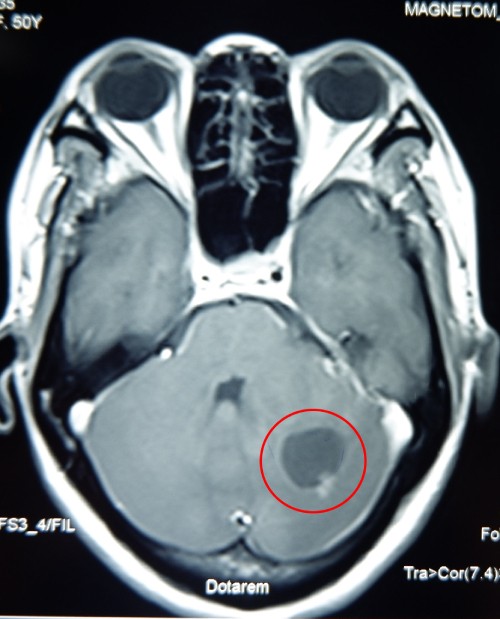

Khối u (trong khoanh tròn đỏ) có kích thước 1,5 cm, to bằng quả quất, nằm sâu trong não nữ bệnh nhân trước khi phẫu thuật. Ảnh: Bệnh viện cung cấp.

Bệnh nhân tự mua thuốc đau đầu về uống, không giảm đau, sức khỏe ngày càng suy kiệt. Bác sĩ Bệnh viện Đa khoa Xuyên Á xác định bệnh nhân có khối u nguyên bào mạch máu não tiểu não (Hemangioblastoma). Khối u nằm ở vị trí rất sâu và phức tạp bên trong não, đã diễn tiến phù tiểu não, giãn não thất.